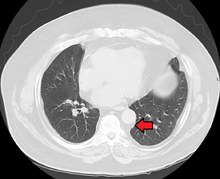

Lipomatosis